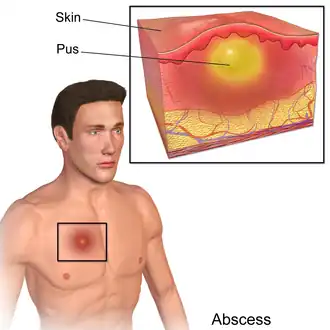

Abscess

-

A diagram of an abscess

A diagram of an abscess -